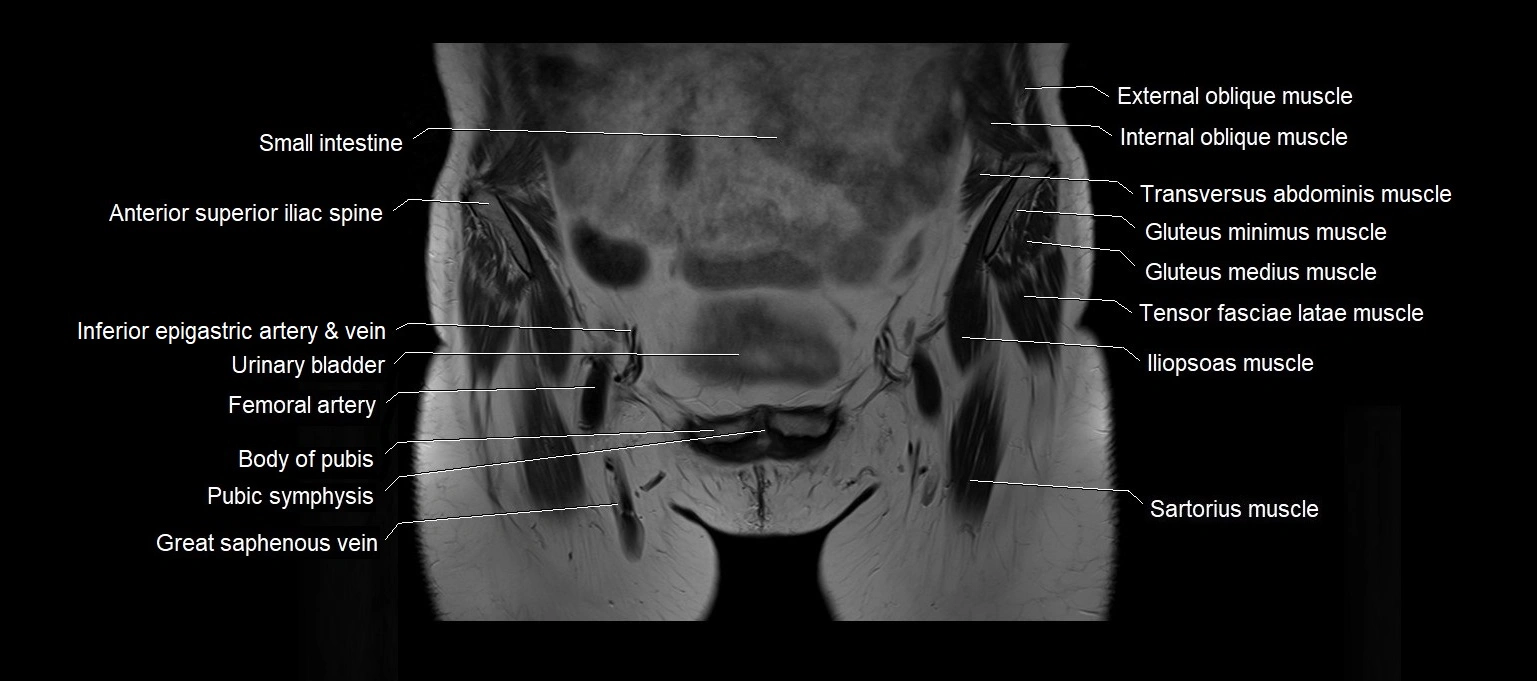

MRI images